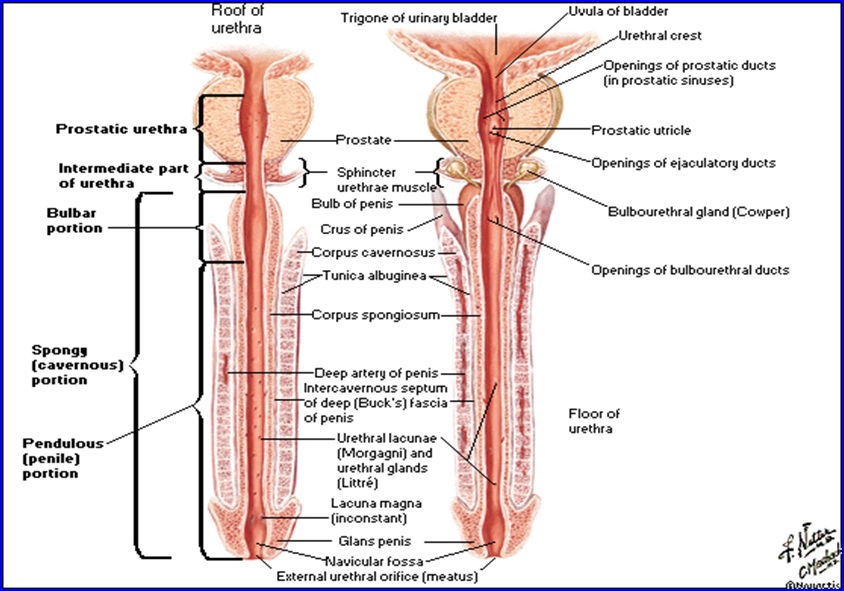

Uretra

Este canalul prin care urina este expulzată din vezica.

Cisto-uretrografie micţională: